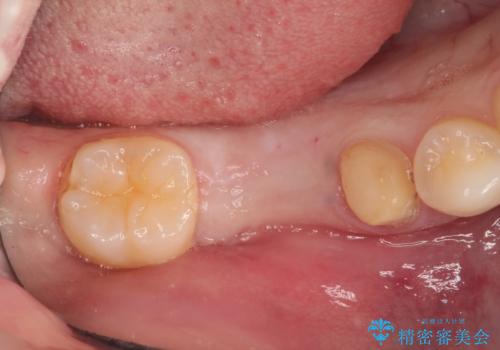

- 右下の奥歯の調子がよくないとのことで来院されました。

レントゲン・口腔内診査をお行い、保存が難しいことがわかりました。

抜歯後インプラントをする計画としました。

見た目では問題がなさそうでも、レントゲン撮影・診査を行うと状態が悪くなっていることがあります。